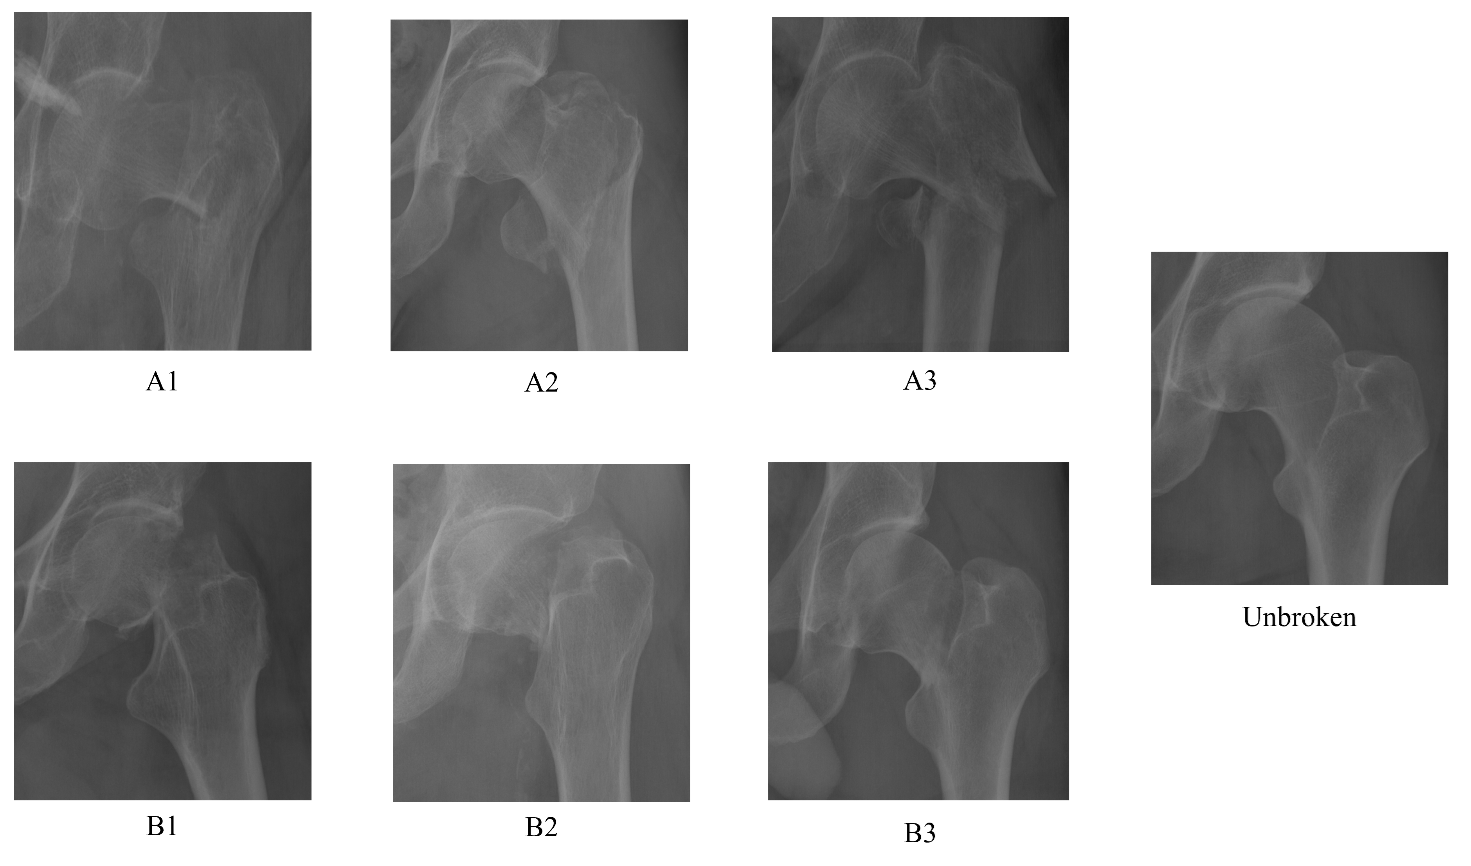

The initial dataset was labelled by a senior trauma surgeon with 18 years of experience, a specialist who has worked specifically on femur fractures in the past 6 years and was composed by n=2645 images of the entire or half hip bone. The dataset was then reviewed using the included radiological referrals and intraoperative diagnosis. All images with discordant classification were analyzed and removed if univocal interpretation by the whole team was not attained. The first step was the segmentation of the images into left and right hips. Then segmentation of the images into left and right hips was performed. The second step was a cleaning phase, where a total of n=242 images were excluded because contained prosthesis (n=97), had poor lighting condition (n=47), showed the area around the femur partially hidden (n=23) or presented a lateral view (n=72). Moreover, because of the low number of C fractures (n=3) detectable on pelvic radiographs, this class was excluded. The third step was a cropping phase, where the areas related to the right and left femur were selected through a fully-automated cropping method and resized to 224×224224224224\times 224, considering the fact that some images present only one between the right and left femur. This technique concerned the use of YOLOv3 (You Only Look Once) [32] algorithm for detection of left and right femur. The fourth step was the revision of the YOLOv3 errors: n=25 femur was not detected, n=1845 right femur were correctly detected while n=208 wrongly detected as left, n=1874 left femur were correctly detected while n=241 wrongly detected as right. After the correction and the manual cropping of the not detected images, the final dataset was composed by n=2152 left femur and n=2055 right femur, which have been flipped horizontally. The fractures were then divided in different types and, afterwards, the dataset was reviewed by two radiologists from our medical team, to confirm the validity of the ground truth. The final number of images was n=4207 manually annotated images divided in different fracture types: 2003 Unbroken femur, 631 type A1, 329 type A2, 174 type A3, 625 type B1, 339 type B2, 106 type B3. This process is shown in Figure 2 following the STARD 2015 flow diagram [33]. Some real X-Rays for each class taken from our dataset are shown in Figure 3.

Refer to caption

Figure 3: Some samples of real X-Rays images used for training the neural network after the cleaning and cropping phase